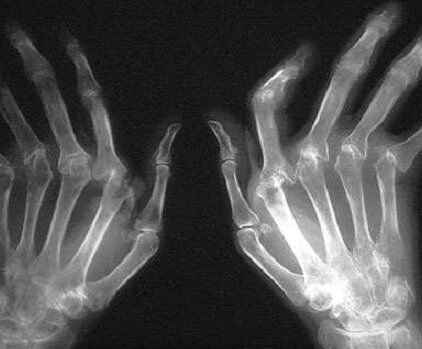

Ревматоидный артрит относится к аутоиммунным патологиям. Характеризуется воспалением хрящевой ткани суставов, которое приводит к их деформации. При данном заболевании симметрично поражаются периферические сочленения рук, запястий, локтей, плеч, бедер и ступней. В тяжелой форме патология проявляется деформацией и эрозией кости. Обычно ревматоидный артрит поражает суставы, но в некоторых случаях возможно распространение воспалительных процессов на внутренние органы разных систем организма.

- Рентгенография.

Обследование должно быть комплексным. Только в этом случае можно получить подробную информацию о протекании заболевания, степени его развития и об общем состоянии здоровья. Ревматоидный артрит суставов нижних и верхних конечностей развивается так же, как и ревматоидный артрит пальцев рук. Первые симптомы патологии не всегда воспринимаются как наличие какого-либо заболевания. Поэтому нередко заболевание диагностируется уже в запущенной стадии, что может усложнить лечение патологии.